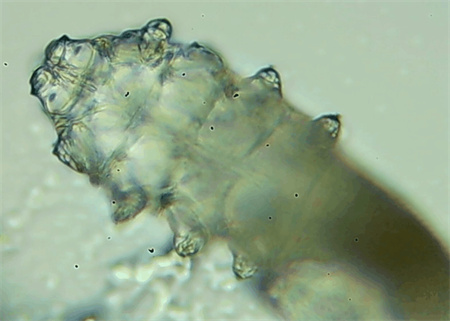

把玻片放到顯微鏡下觀察,通過電腦實(shí)時(shí)傳送的畫面,可以查看到這些拔下來的睫毛上是否有螨蟲。

結(jié)果,有6個(gè)人拔下來的睫毛上都發(fā)現(xiàn)了螨蟲。

這種螨蟲叫做蠕形螨,他們通常呈乳白色、半透明的細(xì)長(zhǎng)狀,擁有四對(duì)腳。它們跟被子上的塵螨可不是同一種。